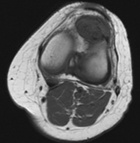

57 year old female presents with c/o L anterior knee pain x5 months. No hx of trauma.

Zoom image: Radiological image Radiological image.